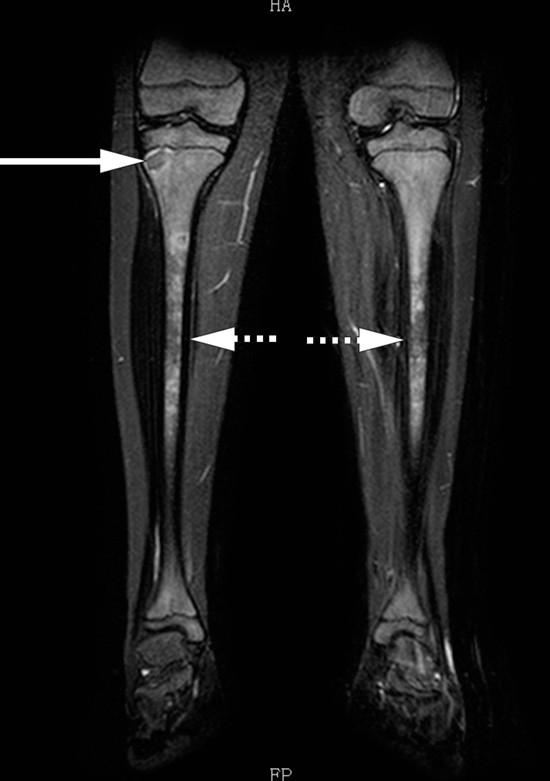

Smertene tiltok, og pasienten holdt seg etter hvert i sengen store deler av dagen. Langs laterale fotrand oppsto det en diskret hevelse. MR av legger og føtter viste multifokale lesjoner i knoklene, ikke typisk for infarkt, tumor eller akutte abscesser (fig 3). Lesjonene liknet heller ikke på leukemiske infiltrater, som typisk har høyere signal i sentrum og mer lokal reaksjon. Samme dag som MR ble tatt, ble det for første gang funnet stigning i leverprøveverdiene. Gammaglutamyltransferase (gamma-GT) var da 111 U/l (10 – 80 U/l) og ALAT 120 U/l (10 – 70 U/l), og SR hadde steget til 50.

Gutten var nå åpenbart systemisk syk, med patologiske funn fra hud, knokkel/beinmarg og lever. Funnene pekte ikke i noen spesifikk retning, men det måtte vurderes om han kunne ha en leukemi- eller lymfomsykdom. MR-funnene kunne tyde på lavgradige abscesser. Leverabscesser var ikke sett ved ultralydundersøkelse en uke tidligere. Det var ingen oppvekst i blodkulturer, men infeksjonssykdom var fortsatt en mulighet. Vaskulitt med beinmargsforandringer kunne ikke utelukkes. Vi mente derfor at beinmargsundersøkelse var nødvendig og at universitetssykehus burde overta utredningen av pasienten.